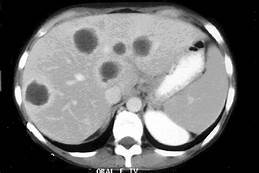

Principal causa de abscesso piogênico hepático, principais agentes, clinica e tratamento?

Abscesso piogênico hepático

Infecções ascendentes da via biliar (mais comum), embolias sépticas da veia cava, bacteremias, contiguidade, criptogênica

E. coli, Klebsiella, s. aureus

Febre de inicio insidioso, dor, inflamação em HD, ictericia, hepatomegalia

Cefalo de 3a + metronidazol // drenagem percutânea